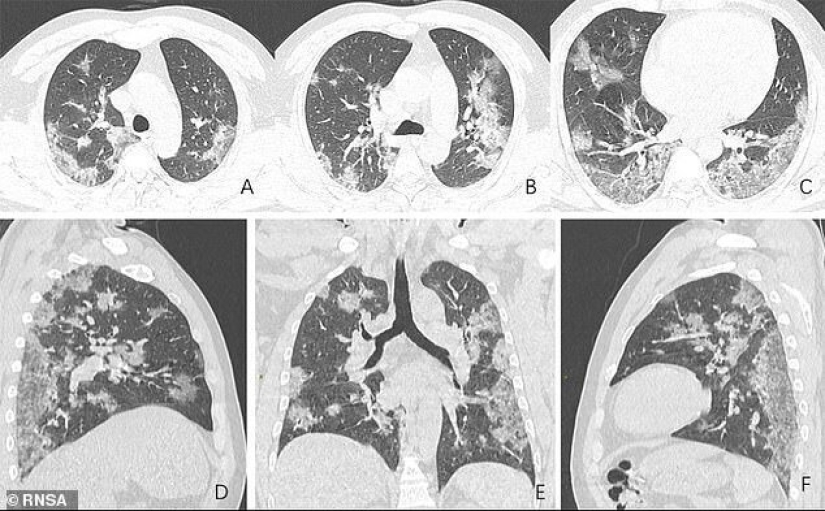

Se han publicado radiografías y tomografía computarizada de un paciente chino de 44 años. Muestran claramente cómo el virus destruye el tejido pulmonar. Según los médicos, las lesiones son similares a las que se encuentran en los pulmones de las víctimas del SARS y el síndrome respiratorio de Oriente Medio.

Los médicos chinos presentaron radiografías y tomografías de los pulmones de un paciente de 44 años que murió de coronavirus. Proporcionan una imagen detallada de cómo el virus destruye los pulmones de una persona.

Las imágenes muestran manchas blancas en la parte inferior de los pulmones. Los médicos los llaman " sellos subpleurales como el vidrio esmerilado."En estas áreas, las burbujas de aire de los pulmones se llenan parcialmente con el contenido. También se observaron lesiones similares en pacientes con neumonía atípica y síndrome respiratorio de Oriente Medio.

El fallecido hombre de 44 años de edad, vivía en Wuhan y trabajaba en el mercado local de mariscos, que probablemente se convirtió en la fuente del nuevo virus. Fue hospitalizado el 25 de diciembre de 2019 después de dos semanas de enfermedad. Los médicos le diagnosticaron neumonía y síndrome de dificultad respiratoria aguda. A pesar del tratamiento, murió una semana después.